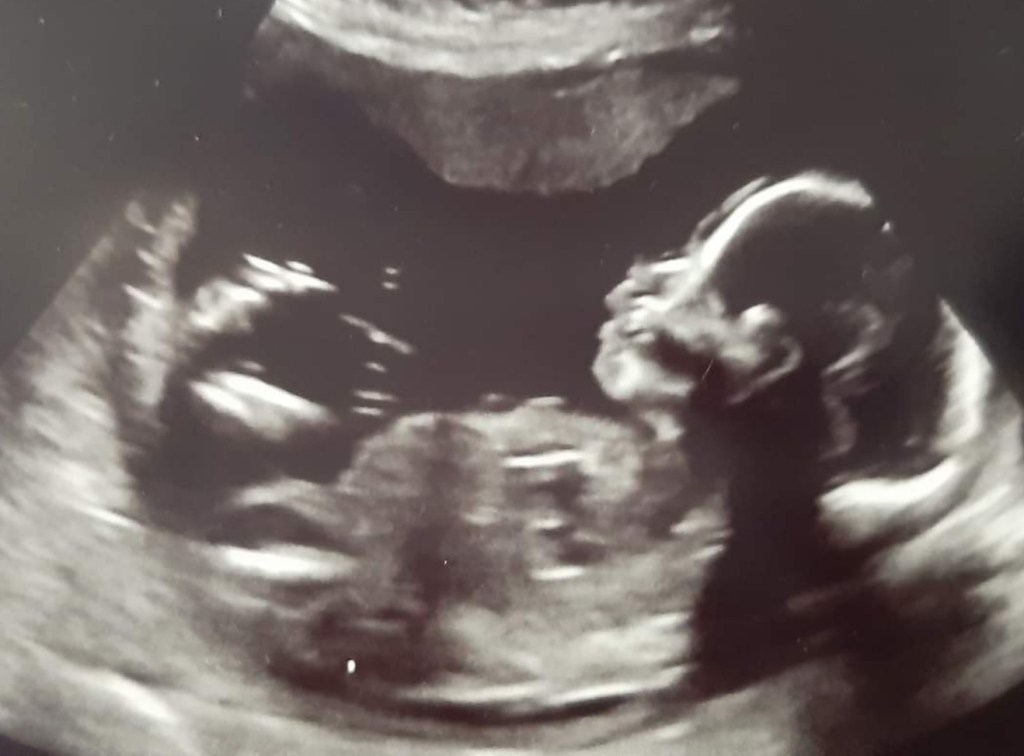

Other symptoms drew in quickly after that: morning sickness, food aversions etc. The extreme fatigue was already there; I had been falling asleep really early in the evening. But I still couldn’t shake this overwhelmingly strong feeling that it was just hormones acting out as a result of a medical problem. So I booked an early pregnancy scan. The external scan immediately showed the yolk sac, and an internal one allowed us to find the heartbeat, check the size etc. It was real… really, actually, very real. I just now had to enjoy it.